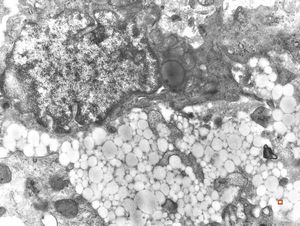

jejunum … lipid malabsorption

M,54y. | duodenum … Whipple disease, foamy histiocyte

lipid malabsorption